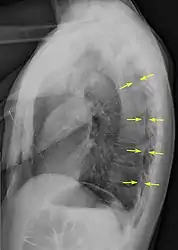

A plain chest radiograph, ideally with the X-ray beams being projected from the back (posteroanterior, or "PA"), and during maximal inspiration (holding one's breath), is the most appropriate first investigation.[25] It is not believed that routinely taking images during expiration would confer any benefit.[26] Still, they may be useful in the detection of a pneumothorax when clinical suspicion is high but yet an inspiratory radiograph appears normal.[27] Also, if the PA X-ray does not show a pneumothorax but there is a strong suspicion of one, lateral X-rays (with beams projecting from the side) may be performed, but this is not routine practice.[14][18]

Lateral inspired X-ray at the same time, more clearly showing the pneumothorax posteriorly in this case